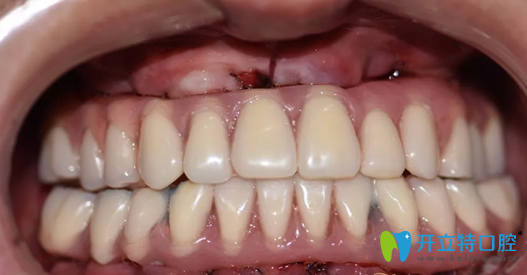

重慶牙博士口腔種植牙術(shù)前照片:

重慶牙博士口腔種植牙術(shù)前照片

這一口牙真的讓人不忍直視,說實話,初看上去真的有點適應不良呀,牙周病如此嚴重,想必莫先生應該被牙痛折磨的不清吧。

種植完即刻牙齒情況照片:

徐孟輝種植完即刻牙齒情況照片

哇塞,這樣的牙齒是不是看上去順眼了很多,如果沒有人說的話,你能看出莫先生的牙是后天種植上去的嗎?